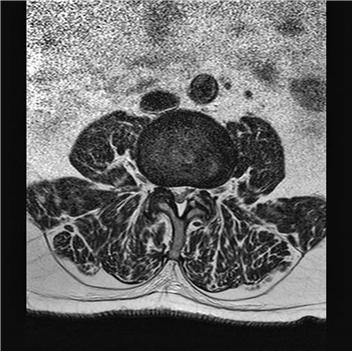

Describe the picture above and name the condition that is demonstrated.

This is an axial MRI scan (T2-weighted) at the L4/5 level that shows hypertrophy of the facet joints, hypertrophy of the ligamentum fl avum, and a broad-based protrusion of the intervertebral disc resulting in severe stenosis of the canal, particularly in the lateral recesses. The condition is spinal stenosis.

What is the common clinical presentation for this condition?

The patient is usually middle aged or older and typically describes gradual onset of low back, buttock, thigh, and calf pain. They may also have numbness, pins and needles, or weakness. The symptoms are exacerbated by walking or even standing. A fl exed position of the spine, e.g. pushing a shopping trolley, is often less painful than en extended position.

Is there an anatomical classifi cation for the condition?

Degenerate spinal stenosis can be divided into:

Zone 1 or subarticular stenosis

Zone 2 or foraminal or pedicular stenosis

Zone 3 or extraforaminal or exit stenosis

What would be your indications for surgery in this condition?

Persistent signifi cant pain despite adequate conservative treatment, including physiotherapy and analgesia. The patient should be fi t enough for general anaesthesia and understand the risk of complications.

When would you perform a fusion in this condition?

The standard operation is decompression. Fusion should be considered in addition when:

z There is a significant spondylolisthesis z There is progressive scoliosis or kyphosis z There is removal of 50 % or more of the facet joints z There is fracture of the pars interarticularis z There is radical excision of the associated disc causing possible anterior destabilization